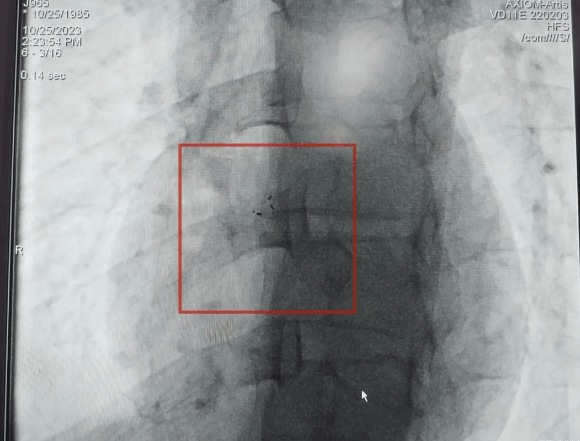

植入體內(nèi)的封堵器